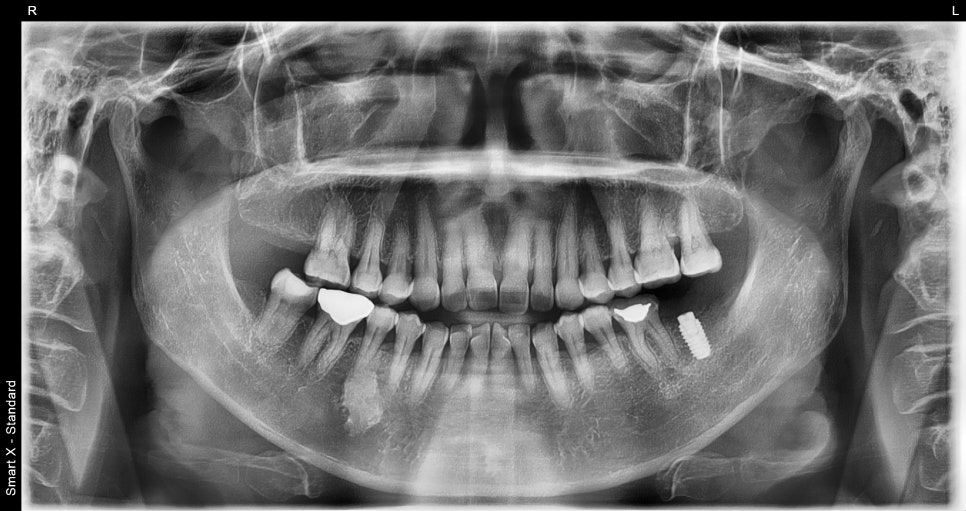

Changes after treatment

After treatment, the patient experienced

restoration of molar chewing function

reduced pain

stable occlusion

They also said it felt comfortable when chewing.

An implant is not just a treatment,

but a treatment that helps restore comfort in daily life.

Molar implants

are not simple placement procedures, but treatments that require precision.

Implant price varies depending on the patient's condition,

and it is important to decide after an accurate diagnosis.

When choosing an implant dental clinic, you should consider not only price but also treatment experience and

systems.